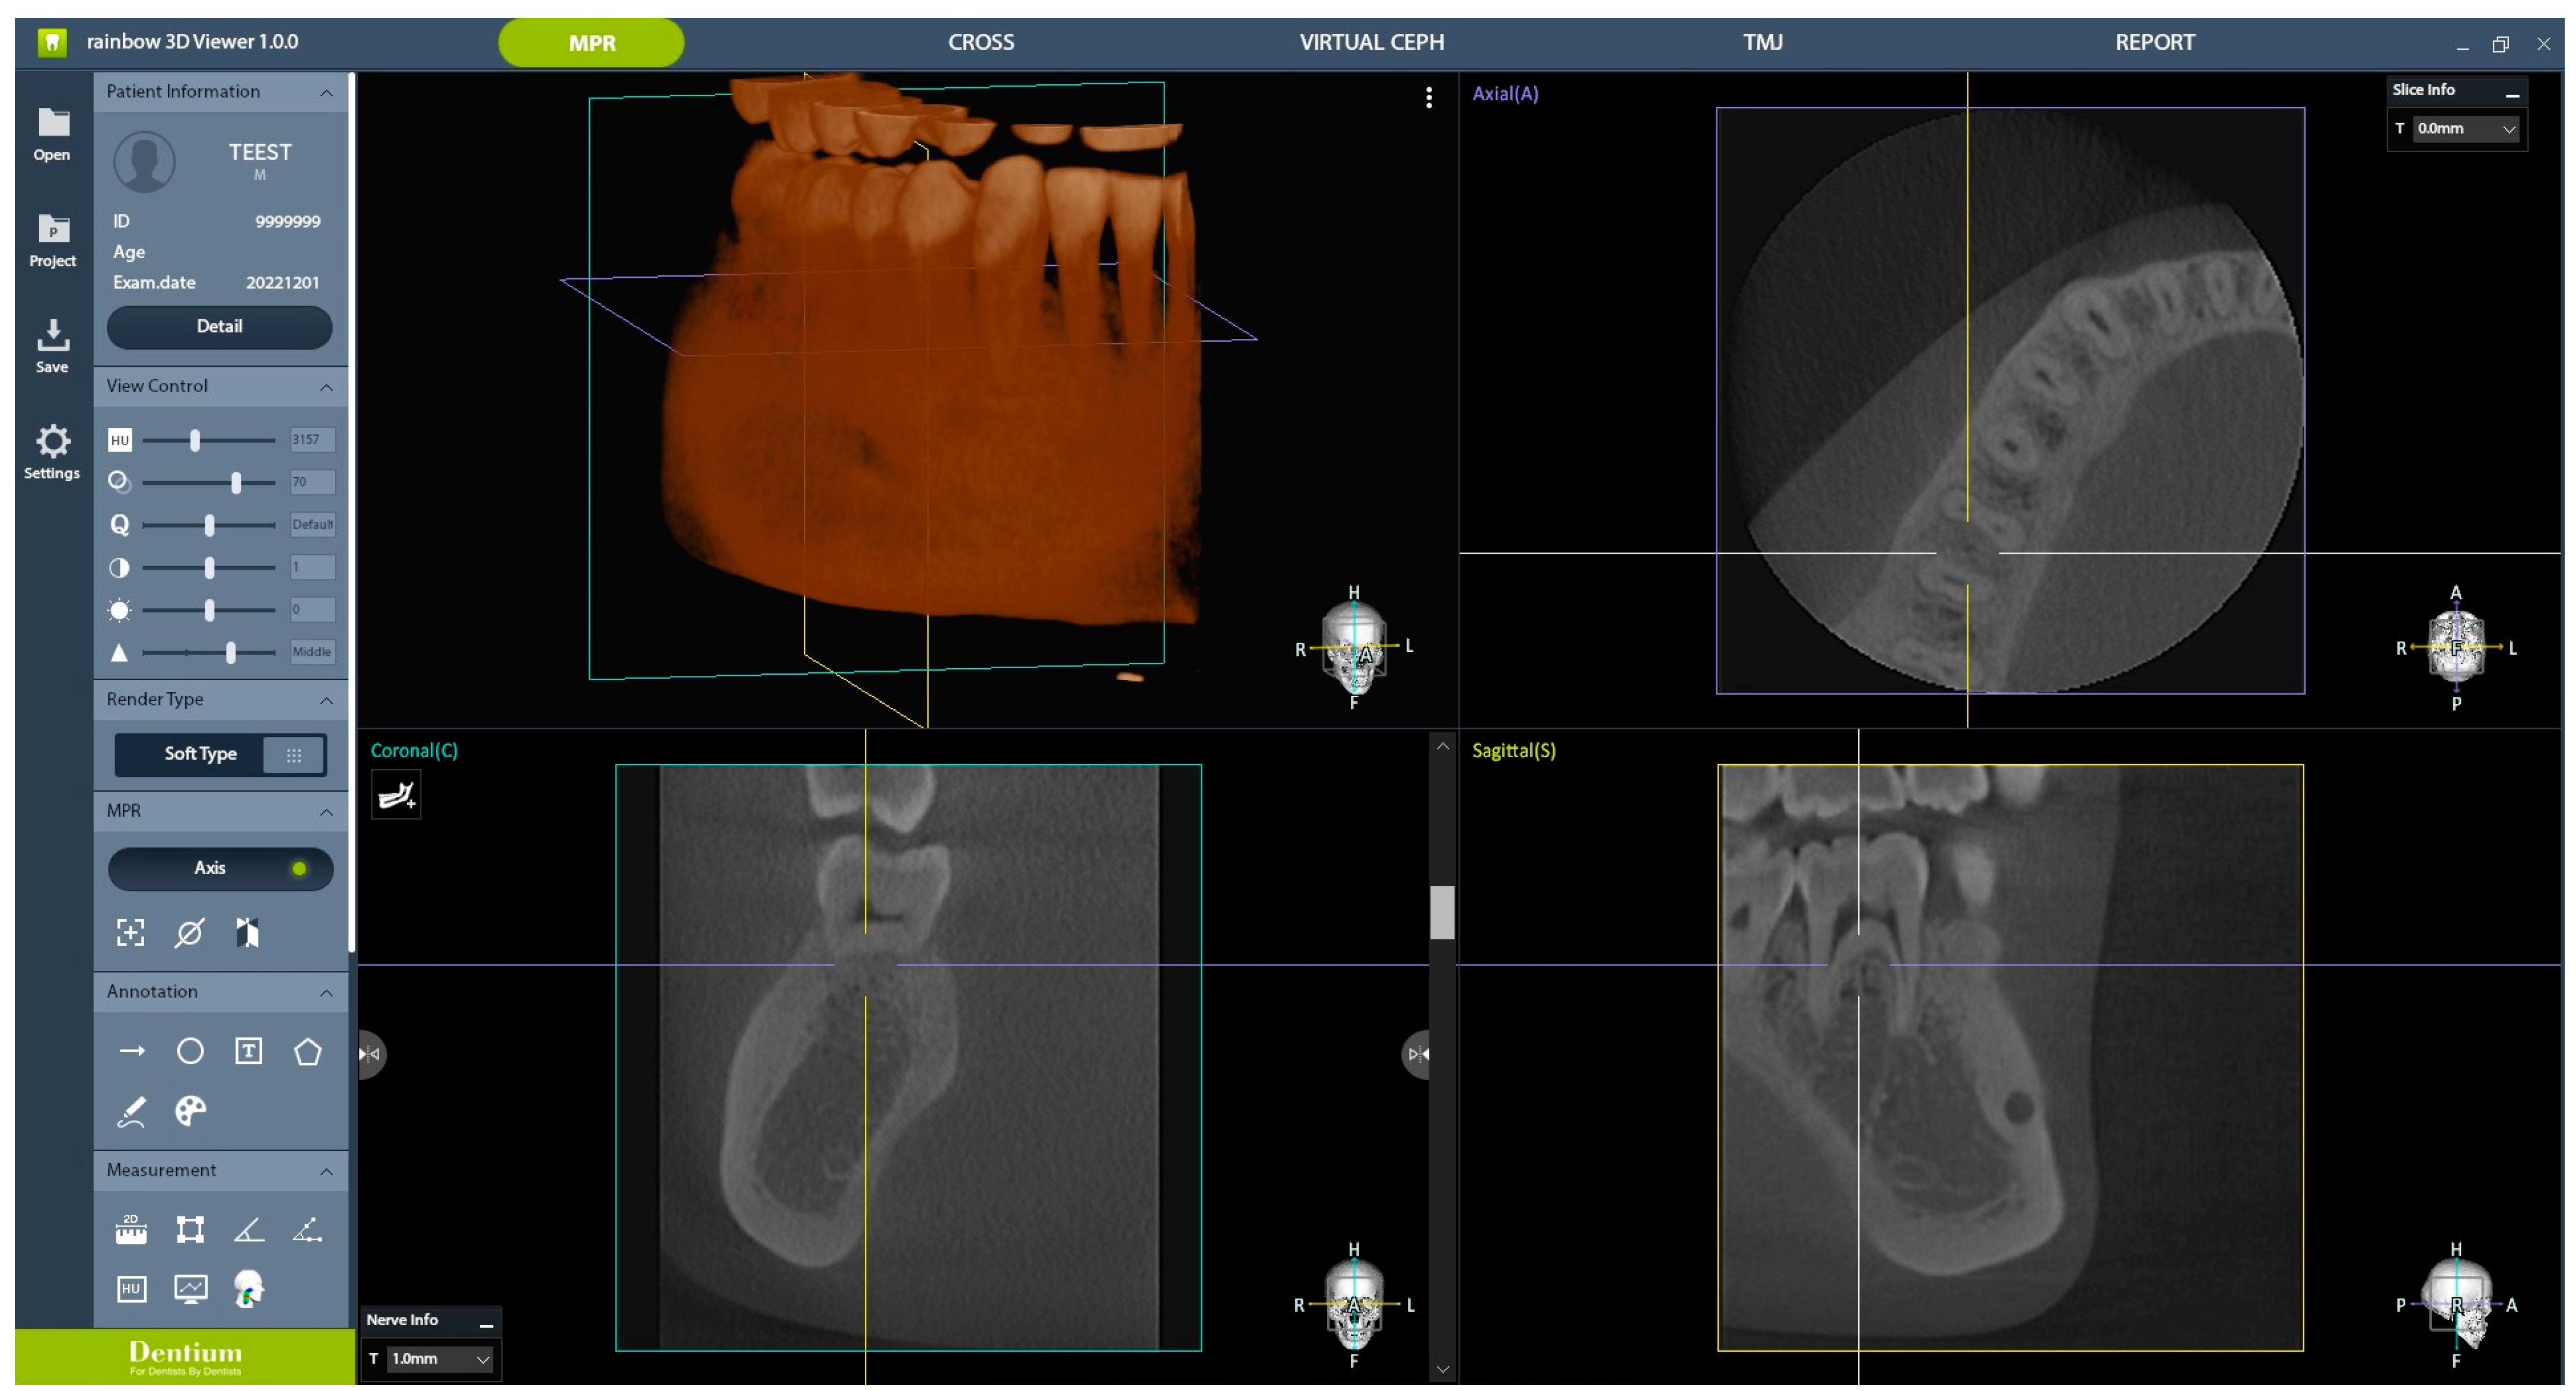

In the experimental group, CBCT images were obtained following protocols 1–4, all of which underwent AI processing, resulting in eight CBCT images centered around the right mandibular first molar. The control group, referred to as protocol 5, had one CBCT image centered around the right mandibular first molar. Therefore, a total of nine images obtained using different protocols were randomly presented for subjective clinical image quality evaluation. Three conservative dentistry specialists and two oral and maxillofacial (OMF) radiology specialists participated in the evaluation. The evaluation criteria comprised 11 parameters, as follows: (1) number of roots, (2) number of root canals, (3) enamel–dentin differentiation, (4) lamina dura, (5) periodontal ligament (PDL) space, (6) trabecular pattern, (7) cortex of the alveolar crest, (8) cortex of the mandibular canal, (9) furcation, (10) cortex of the mandible, and (11) overall image quality for periapical lesion diagnosis. Participants rated their responses on a six-point scale: (1) strongly disagree, (2) disagree, (3) slightly disagree, (4) slightly agree, (5) agree, and (6) strongly agree. Images were presented to the evaluators using the Rainbow 3D viewer 1.0.0 (Dentium, Suwon, Republic of Korea), which allows axial, coronal, and sagittal views of CBCT images for evaluation (Figure 4). This is the same program used to capture actual CBCT images in clinical settings and for diagnostic evaluation. To ensure fairness, an observation time of 3 min was allotted for each image. To investigate intra-rater reliability, subjective clinical image quality evaluations were performed twice by the same evaluators, with a 2-month interval in between, to allow for a washout period.

Figure 4.

The images presented to the evaluators for subjective clinical image quality evaluation.